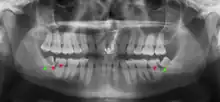

Impacted wisdom teeth are classified by their direction of impaction, their depth compared to the biting surface of adjacent teeth and the amount of the tooth's crown that extends through gum tissue or bone. Impacted wisdom teeth can also be classified by the presence or absence of symptoms and disease. Screening for the presence of wisdom teeth often begins in late adolescence when a partially developed tooth may become impacted. Screening commonly includes a clinical examination as well as x-rays such as panoramic radiographs.

If the tooth cannot be assessed with clinical exam alone, the diagnosis is made using either a panoramic radiograph or cone-beam CT. Where unerupted wisdom teeth still have eruption potential several predictors are used to determine the chance of the teeth becoming impacted. The ratio of space between the tooth crown length and the amount of space available, the angle of the teeth compared to the other teeth are the two most commonly used predictors, with the space ratio being the most accurate. Despite the capacity for movement into early adulthood, the likelihood that the tooth will become impacted can be predicted when the ratio of space available to the length of the crown of the tooth is under 1.[5]: 141

There is no standard to screen for wisdom teeth. It has been suggested, absent evidence to support routinely retaining or removing wisdom teeth, that evaluation with panoramic radiograph, starting between the ages of 16 and 25 be completed every 3 years. Once there is the possibility of the teeth developing disease, then a discussion about the operative risks versus long-term risk of retention with an oral and maxillofacial surgeon or other clinician trained to evaluate wisdom teeth is recommended. These recommendations are based on expert opinion level evidence.[19] Screening at a younger age may be required if the second molars (the "12-year molars") fail to erupt as ectopic positioning of the wisdom teeth can prevent their eruption. Radiographs can be avoided if the majority of the tooth is visible in the mouth.